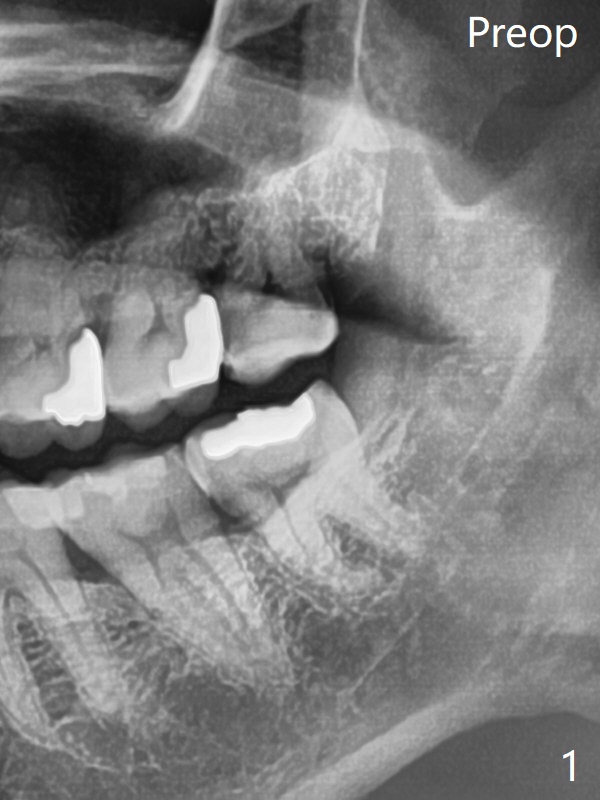

Xin Wei, DDS, PhD, MS 1st edition

10/16/

2020, last revision 10/17/2020